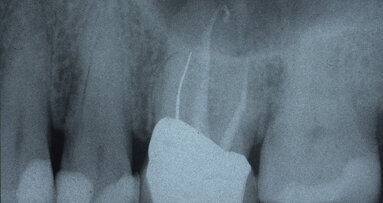

Following what seemed to be a root canal failure in tooth No. 14 based on clinical and radiographic diagnosis with a conventional two-dimensional periapical...

“Wow, I can’t believe how cone beam 3-D imaging has changed the way we practice.” That’s a strong statement coming from a ...